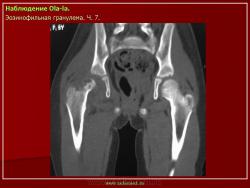

Из опубликованных наблюдений н сайте.